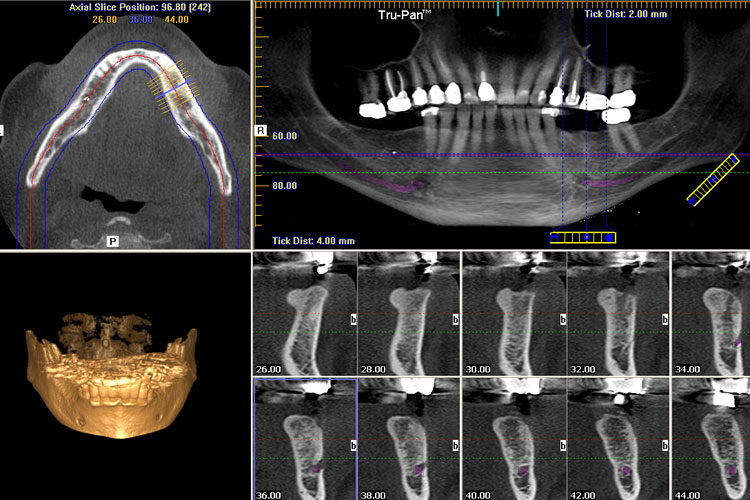

Cone beam CT scanning, otherwise known as Cone beam computed tomography, is a medical imaging technique that consists of capturing three dimensional (3D) images of the patient’s mouth, jaw, nose, ears and throat. Compared to a conventional CT scanner, the use of a cone shaped x-ray beam dramatically reduces the amount of radiation that is emitted from the scanner, making it much safer for the patient. In dentistry, the Cone Beam CT scanner is used when regular facial radiographs (x-rays) are not sufficient enough. Because it is quick and efficient, this technological advancement has become an important tool in the treatment planning and diagnosis in the context of implant surgery, the evaluation of potential abnormalities in a patient’s teeth, visualizing and diagnosing dental trauma and in several other applications.

Using 3D CBCT scanners, we can ensure that the implants are surgically placed in a manner that compliments your natural oral anatomy and the long term success of the procedure.